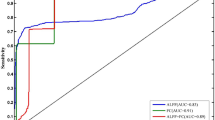

Abnormal ReHo between MDD patients with SD and MDD patients without SD represented as feature variables (1 = right PCC/precuneus, 2 = right MCC, 3 = right ITG, 4 = left postCG), which were entered into the classification models. The combination of the ReHo values of 3 and 4 (Table 3; Fig. 4) could optimally discriminate MDD patients with SD from those without SD with accuracy, sensitivity, and specificity rates of 84.21% (48/57), 87.50% (21/24), and 81.82% (27/33), respectively.

Visualization of classifications through SVM using the combination of ReHo values in the right ITG and left postCG (features 3 and 4) to discriminate MDD with SD and MDD without SD. Left: Confusion matrix map of the combination of ReHo values in the right ITG and left postCG. The target class conveys the correct classification of each subject. The output class conveys the predicted classification of each subject. Red boxes represent incorrect predictions, and green boxes represent correct predictions. Right: 3D visualization of SVM with the best parameters. Log 2c and log 2 g mean the range and step size of the given parameters c and g (c and g are the parameters of the kernel functions in SVM training). ReHo, regional homogeneity. Pa_s, major depressive disorder with sleep disturbances; Pa_ns, major depressive disorder without sleep disturbances; SVM, support vector machine; postCG, postcentral gyrus; ITG, inferior temporal gyrus